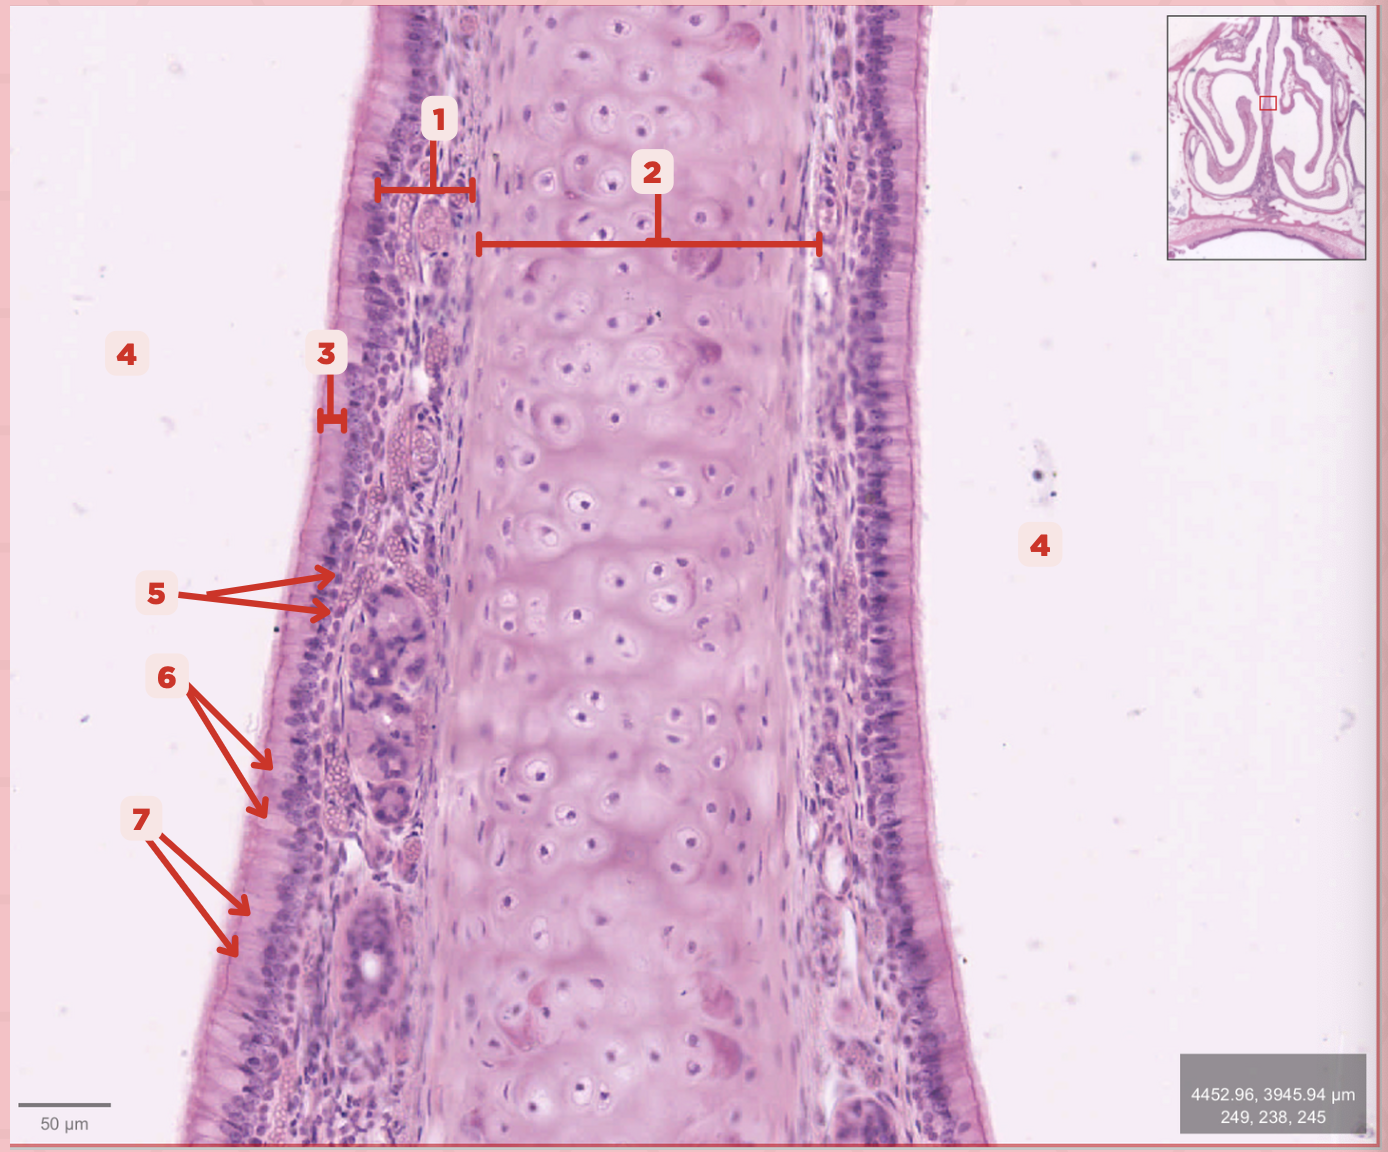

Identify the structure labeled as 1.

Hyaline Cartilage

Identify the structure labeled as 2.

Respiratory Epithelium

Identify the structure labeled as 3.

Nasal Cavity

Identify the structure labeled as 4.

Basal Cells

Identify the structure labeled as 5.

Goblet Cells

Identify the structure labeled as 6.

Ciliated Columnar Cells

Identify the structure labeled as 7.

Adipose tissue

What type of tissue is sometimes seen between the bony spicules?

Serous and Mucous Glands

What glands are present in the Lamina Propria?